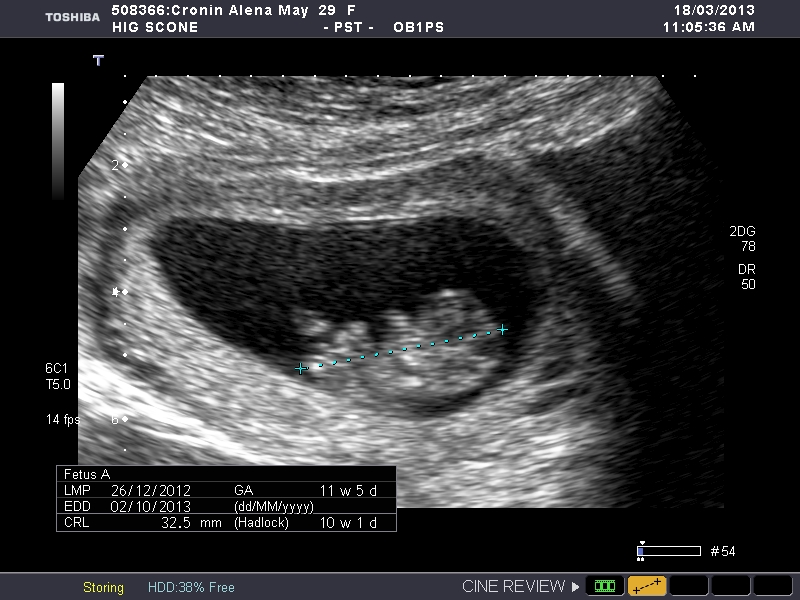

So maybe to early I had a date scan yesterday 10.2 weeks and I read on the net that for nub theory you have to be 10-14 weeks so I thought I would post here so we can guess. My next scan is at 13 weeks so I will post them to and I can compair. So what do you think boy or girl? I am desperate to know.

Attachment 9734

Attachment 9735